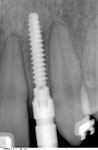

Zustand 9,5 Jahre nach Implantation